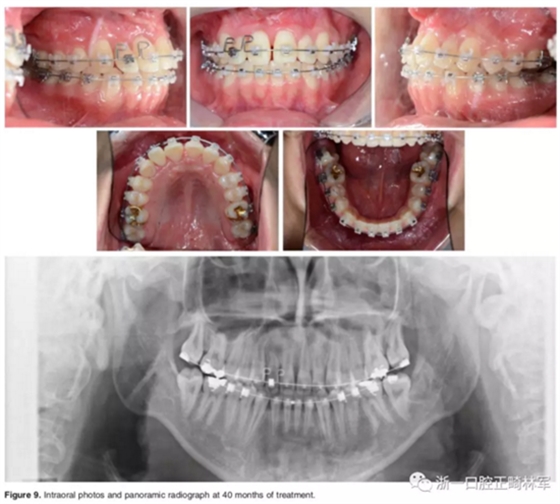

結束階段:

治療40個月后,3顆阻生牙位置已靠攏,繼續(xù)進行排齊。使用高轉矩托槽及帶L型曲的0.019*0.025-inch Beta鈦絲對側切牙進行轉矩控制,再在雙頜使用0.019*0.025-inch不銹鋼絲進行排齊。矯治結束后,去除托槽、弓絲,雙頜前牙區(qū)粘接保持器。

總療程約50個月。

口外相:前牙易位、阻生均得以正確糾正,牙周組織健康。

口內相及模型:I類尖牙、磨牙關系,覆合、覆蓋正常;中切牙與側切牙間有輕微的轉矩差;牙齦外形可;此外,在治療期間病人的口腔衛(wèi)生不夠良好,導致幾顆牙齒出現了齲病。

影像學:頭顱側位片示:矢狀向和垂直向骨骼發(fā)生變化(ANB角,3°;SN-MP,51°);上頜切牙略前傾(U1-SN,106°),與下頜切牙一致(IMPA,75°);病人的面部輪廓得以保持。全景片示:由于牙齒萌出,上前牙區(qū)垂直向牙槽骨水平增加;雖然前牙牙根較彎曲,但其平行度仍可,且無明顯的牙根吸收。CBCT示:前牙唇側骨質連續(xù)性改善,牙根唇側支持組織變好,牙槽骨高度、厚度均有增加,但轉矩的改變一定程度上導致了局部應力的增大。